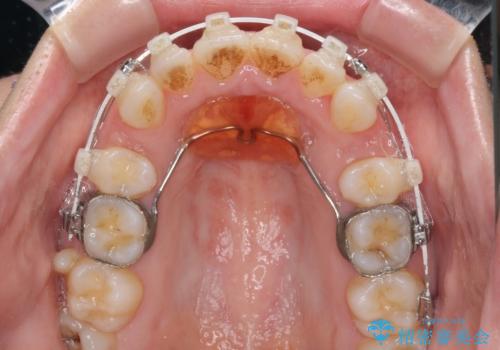

- 前歯のデコボコと口元の突出感を気にして来院された患者様です。

上下左右第一小臼歯4本を抜歯し、ワイヤー装置にて口元を引っ込めるよう矯正治療を行うこととしました。

叢生が強かったため、口元の突出感の改善には限界がありましたが、横側からも口元が引っ込んだ感じが分かるほど改善されました。